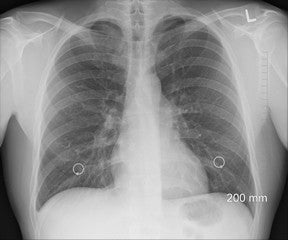

Recreational scuba diving can have significant effects on the body including increased blood pressure, but this shouldn’t pose a risk if you’re fit and healthy. If you have heart disease, high blood pressure, angina, diabetes or if you’ve suffered a stroke consult your doctor before diving.

Scuba diving can be hard on your heart due to the increased blood pressure when diving, as breathing air under pressure when scuba diving affects your heart and circulatory system.